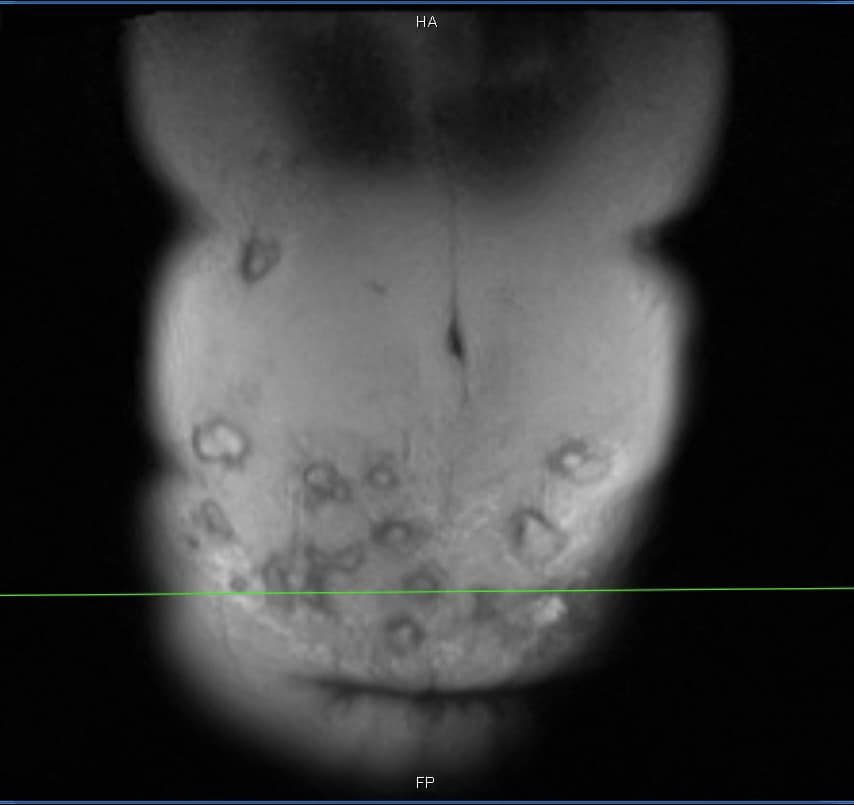

Ổ áp xe trên ổ bụng.

Bác sĩ Minh cho biết, vùng thành bụng bệnh nhân bị viêm phản ứng nặng, vùng da ngoài thành bụng đỏ, nổi gồ ghề, sờ bên dưới có hàng chục khối tổ chức vón cục, áp xe....

“Bệnh nhân này có thể tạo hình lại thành bụng, đồng thời giải quyết được 20 khối áp xe lớn nhỏ. Tuy nhiên, do vùng tiêm rộng nên việc lấy hết ổ áp xe này không dễ dàng. Với những khối áp xe tiêm ở vị trí cao như hạ sườn thì quá trình xử lý sẽ để lại sẹo, gây mất thẩm mỹ”, bác sĩ Minh chia sẻ.